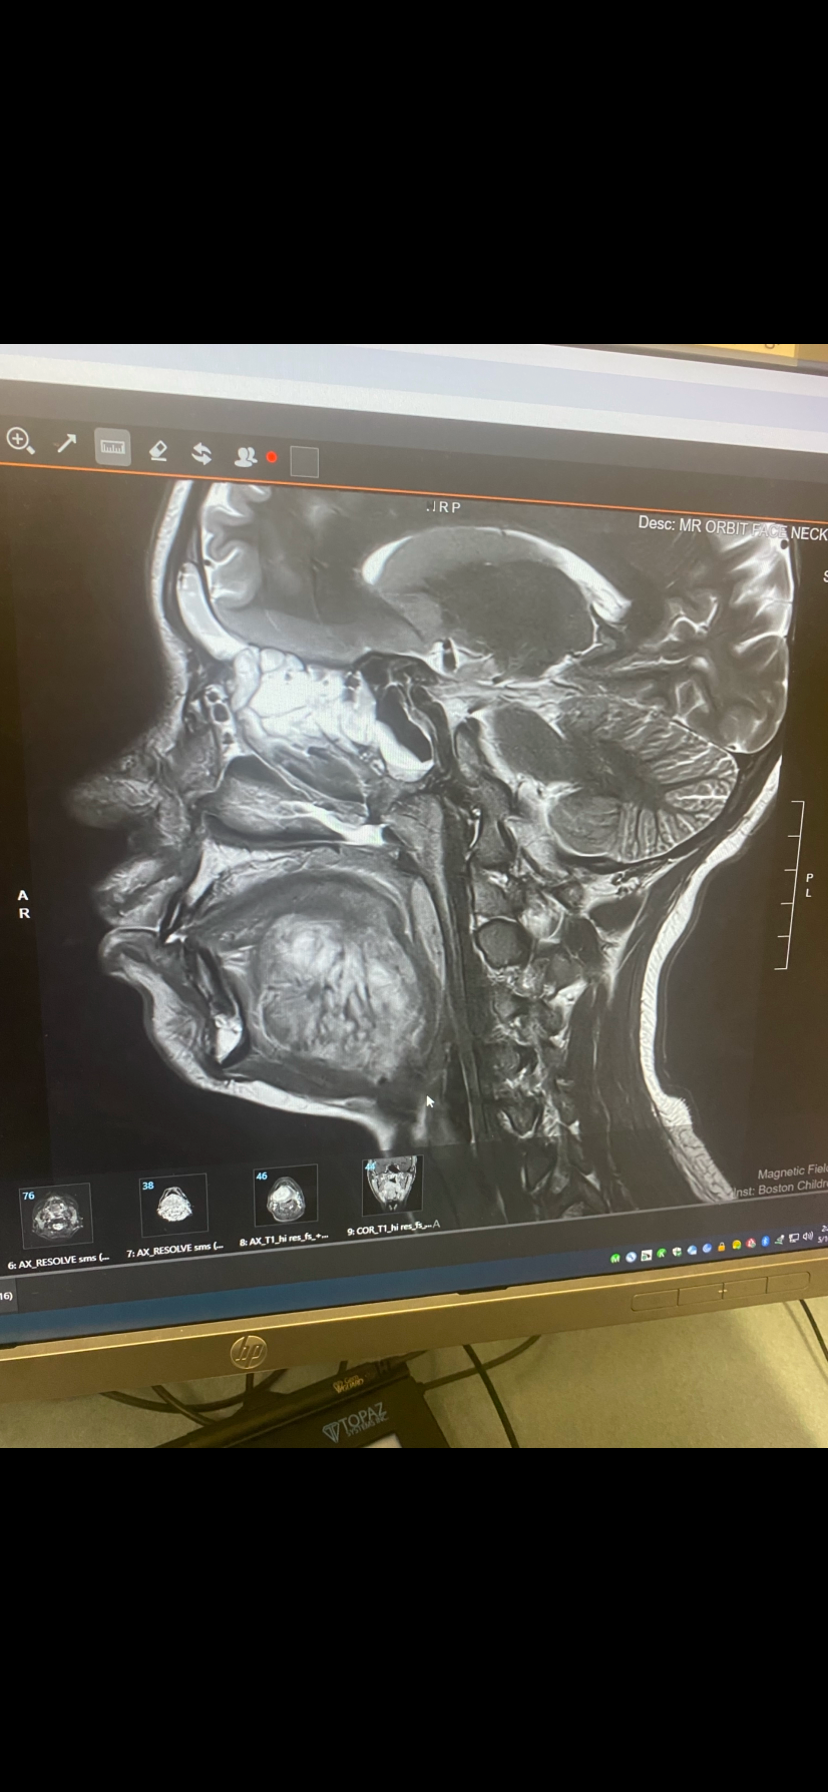

On March 6th, 2025, was an appointment we'd all been anxiously waiting for at Boston Children's Hospital. That day, the doctors found a 2 1/2 inch mass under her tongue. Since then, Amiyah has had a biopsy, CT scans/PET scans, then surgery again to put her port in.

Amiyah celebrated her 15th birthday on March 21st! Today, on Tuesday, March 25th, she got her final diagnosis: She has a rare type of Sarcoma, Desmoplastic Small Round Cell Tumor (DSRCT), a battle no child should have to face. it was a complete shock to all of us. Chemotherapy starts tonight and she is preparing to fight one of the toughest battles of her life. But if you know our beautiful Amiyah, you know she is a fighter, and she is so strong, courageous, and always full of light.

Amiyah's treatment plan involves chemotherapy at Dana-Farber Jimmy Fund, also radiation, and multiple surgeries. Her journey will be challenging, but she faces it with unwavering strength and a heart full of hope and faith.